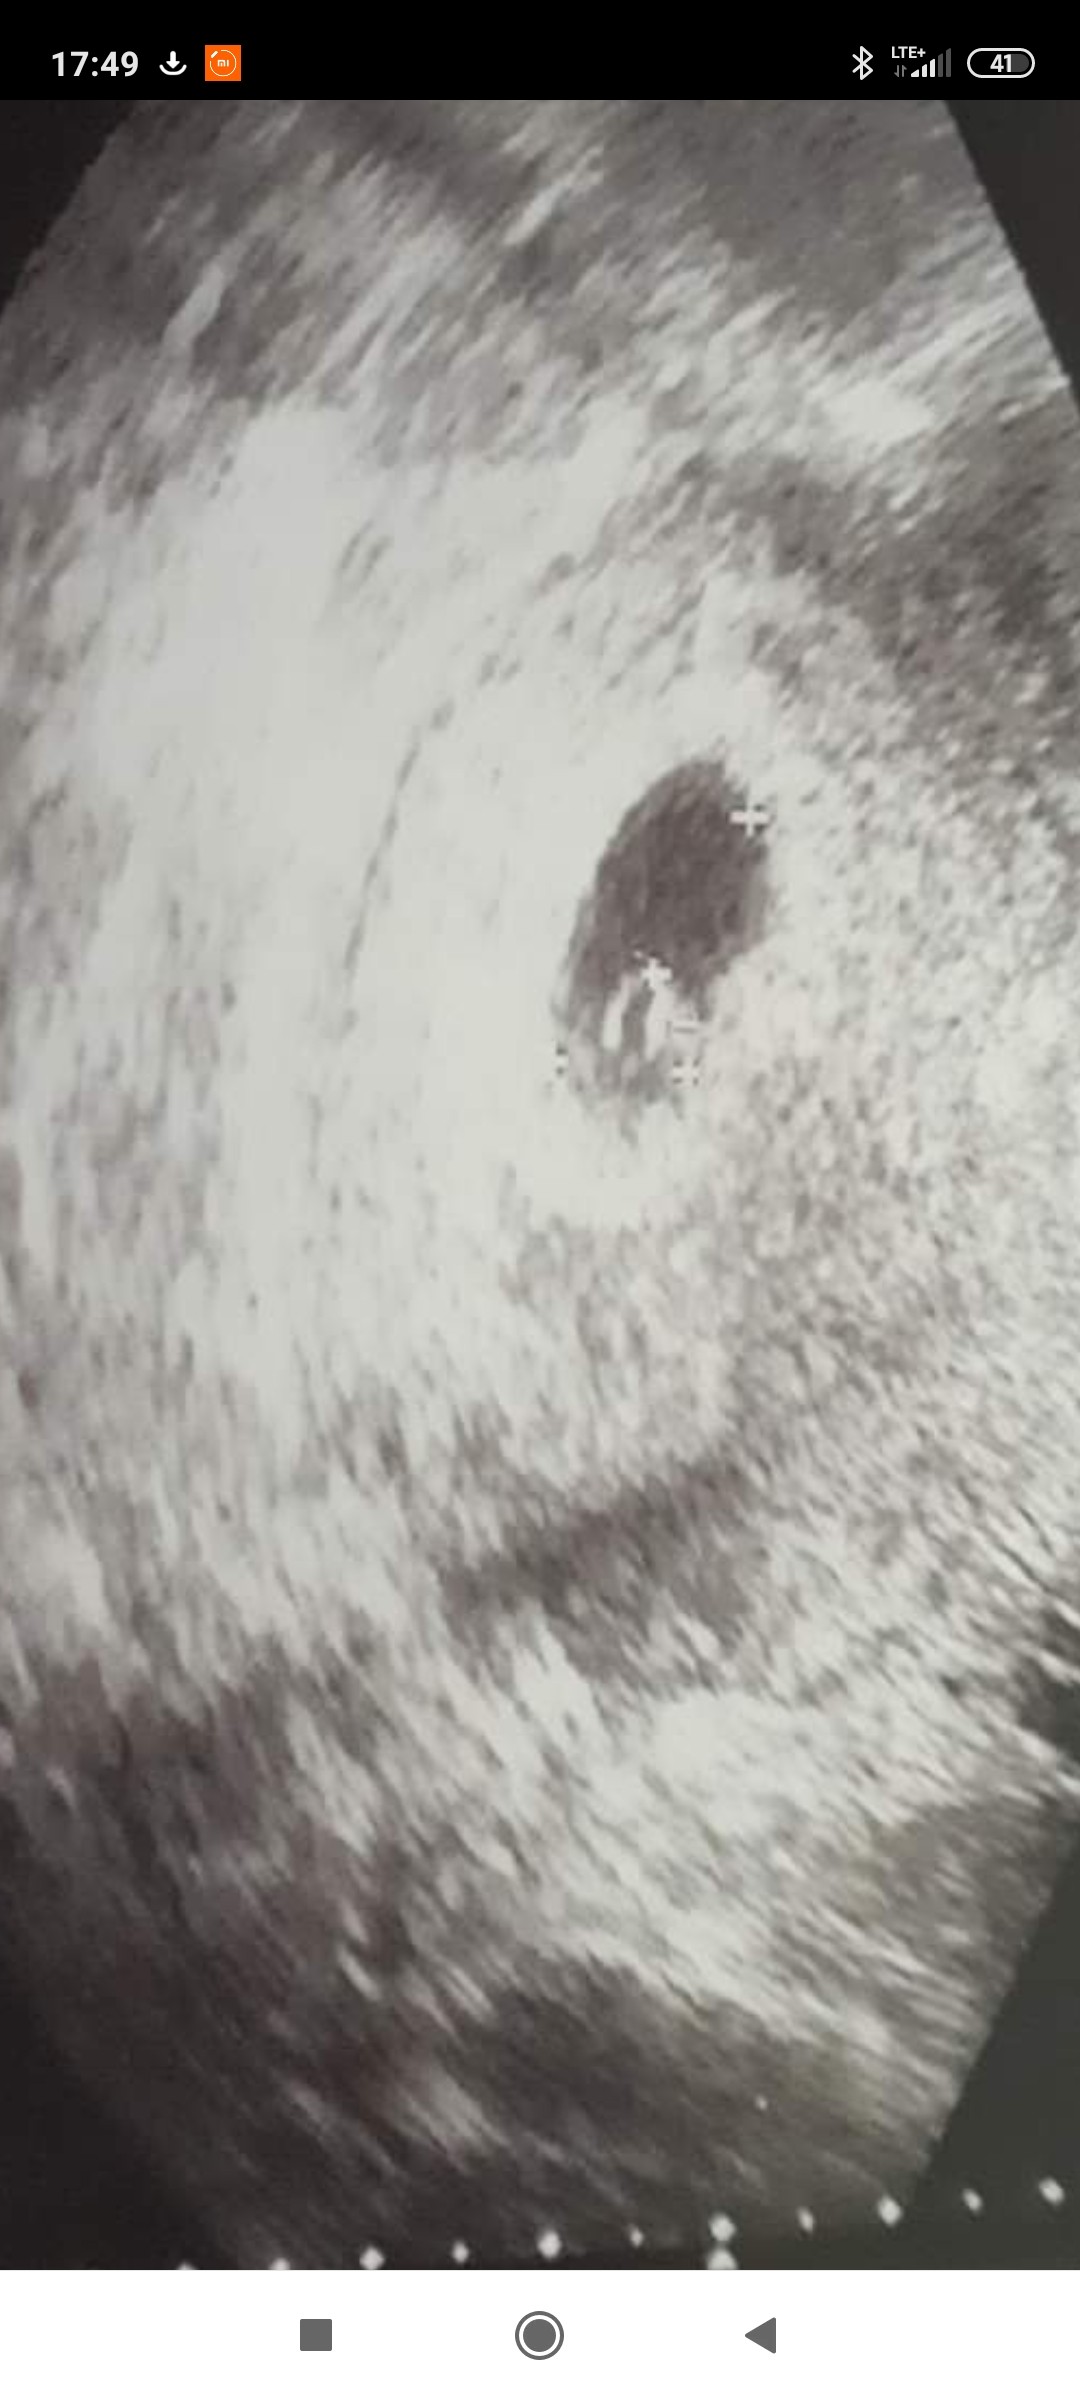

Już po badaniu . Pęcherzyk ma 6 mm a w srodeczku malusienki zarodek 🥰i przebłyski pulsowania 😍. Także niewiem czy nie skończę na styczniowych mamuskach 😍 ale na to dokładnie poczekam do 14 czerwca .

To moje zdjęcie z 6 tc z poprzedniej ciąży. Też nie jest wyraźne napewno następne będą już wyraźniejsze

pewnie tak, a u mnie dopiero 5w0d, więc ten pęcherzyk jest malutki [emoji3064] nie wiem, chyba w poniedziałek pójdę z wynikami badań, to może znowu spojrzy i coś więcej juz będzie